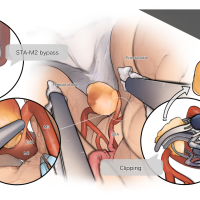

術後イラストシリーズ